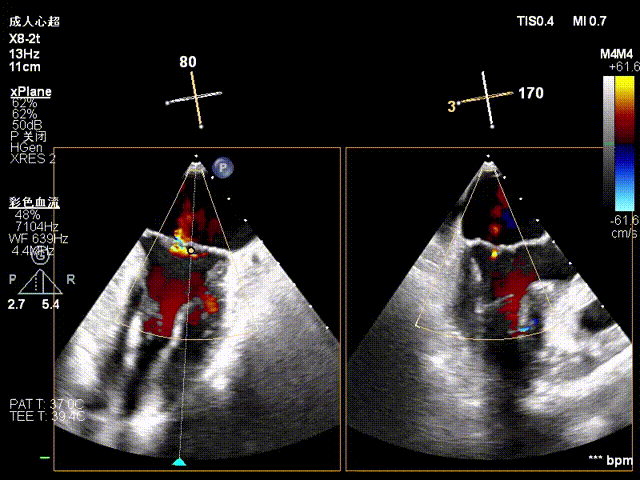

The operation was performed in a hybrid operating room and completed under the guidance of real-time three-dimensional transesophageal echocardiography (3D TEE) and X-ray fluoroscopy throughout the entire process.

Mitral Valve Repair Stage: Via the transfemoral venous approach, a 4.0 cm atrial septal puncture was performed, and one mitral valve clip was selected. The unique feature of wide-angle deployment effectively resolved the issue of excessive leaflet tension during valve clip closure. Under the precise guidance of ultrasound, one clip was successfully implanted at the site of the widest regurgitation in the A2-P2 segment of the mitral valve. Immediate postoperative TEE assessment showed that mitral regurgitation was reduced to trivial (1+), the mean transvalvular pressure gradient was only 3 mmHg, and pulmonary venous retrograde flow was significantly improved.

Clip Closure Following Leaflet Capture

Regurgitation Essentially Eliminated at 25° Closure

Trivial Residual Regurgitation Post Deployment

Stable Tissue Bridge

Transvalvular Pressure Gradient of 3 mmHg

Tricuspid Valve Annuloplasty Stage:Subsequently, via the right internal jugular vein approach, the K-clip® transcatheter tricuspid valve annuloplasty system was delivered to the right atrium. With the assistance of three-dimensional ultrasound stereoscopic views, a 12T clip was successfully implanted at the posteroseptal commissural annulus of the tricuspid valve, and a 14T clip at the anteroposterior commissural annulus, achieving effective constriction of the dilated annulus. Immediate postoperative assessment demonstrated that tricuspid regurgitation was improved from severe (4+) to mild (1+) instantaneously.

1.Intraoperative baseline assessment of regurgitation severity

2.Placement of large sheath and delivery system under ultrasound guidance

3.Steer and rotate the delivery system to target the lesion, and implant the anchor screw via the 3D MPR plane

4.Land the clamping arms after orientation adjustment, and close the clamping arms slowly

5.Perform the same procedure for the second clip; the clip morphology is stable under 3D imaging